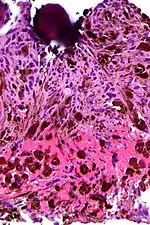

Micrograph of a psammomatous melanotic schwannoma with a psammoma body, as may be seen in Carney complex. H&E stain.

- Psammomatous melanotic schwannoma

Psammoma bodies usually have a laminar appearance, are circular, acellular and basophilic.